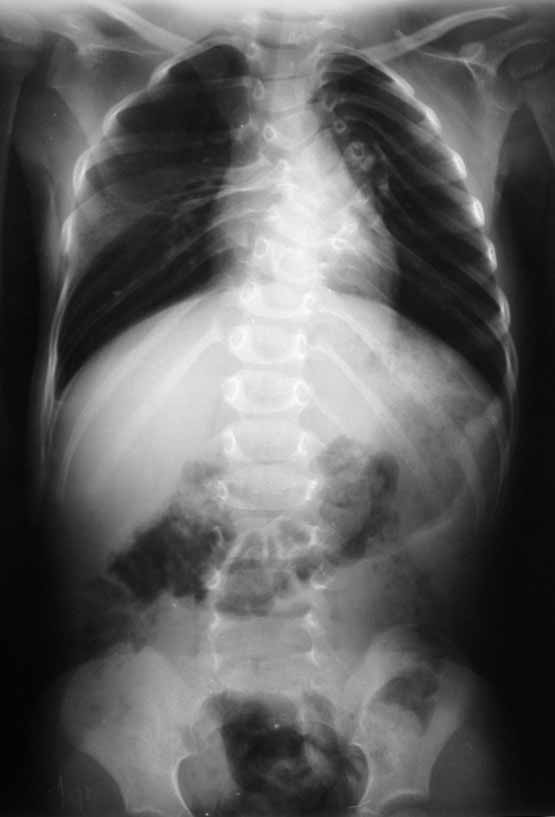

Уважаемые коллеги!Выскажите, пожалуйста, мнения о тактике лечения данной

пациентки.Девочка, 5 лет.ДЗ: Врожденный S образный сколиоз, аномалия развития

позвоночника: клиновидные 5 6 грудные позвонки, аномалия развития грудной клетки:

деформация ребер. Анамнез заболевания: Болеет с рождения, начала ходить в 1,5 года. В 5

месяцев мама отметила наличие реберного горба, который увеличивался в размерах, в 1год 10

месяцев произведена рентгенография позвоночника отмечена его деформация. Заранее